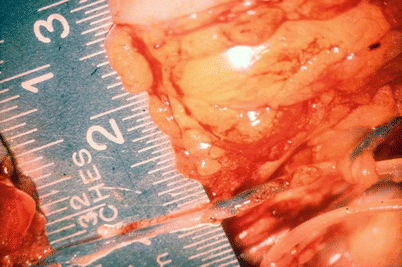

3.3.2 End-to-End Anastomosis

The first stitch is the most difficult one since the wall is collapsed. It might be helpful to add a small amount of Ringer’s solution mixed with heparin helping to lift the wall (Fig. 3.3). In very small lymphatic vessels with fibrosis around the lumen, it might be advisable to only fix the outer layer with the stitches. The content of the lumen of the vessel can then drain into the graft.

End-to-end anastomosis, first corner stitch. Graft with translucent wall above, sclerosed lymphatic vessel of lymphedematous tissue with the lumen surrounded by fibrosed wall below (© Baumeister)

The back wall is just lifted when starting to anastomose. The first stitch is placed at the far end of the vessels.

The sutures are directed from outside to inside and back on the opposite wall.

The second corner stitch is placed in front of the surgeon.

The suture is finished with the closure of the front wall.

Care should always be taken to avoid tension to the lymphatic vessel wall in oblique direction.

In longitudinal direction the vessel as a whole is however remarkable resistant against tension.

The number of stitches is dependent on the size of the lymphatic and the condition of the vessel wall.

Very small lymphatic vessels may just be adapted by one single stitch.

Danese (1982) had shown experimentally that lymphatic collectors may perform anastomosis by themselves if they come close to each other. This is encouraging for the microsurgeon. He will learn to minimize the disturbance for the lymphatic vessel.

In middle-sized lymphatic vessels, three to four stitches are enough.

Leakage will not be a problem since the pressure is low (Fig. 3.4).